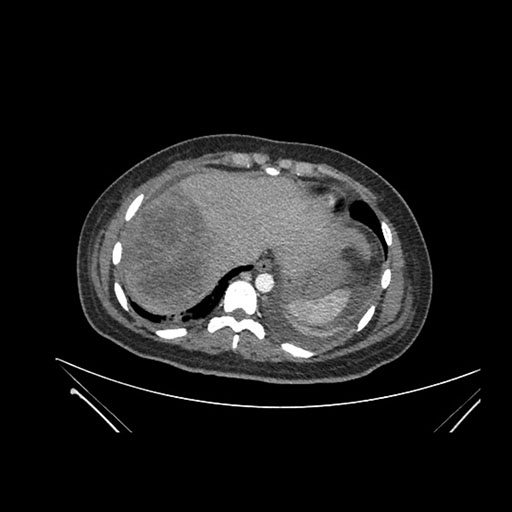

Axial Arterial

Imaging analysis

Based on initial findings, which issue(s) would you be most concerned about?